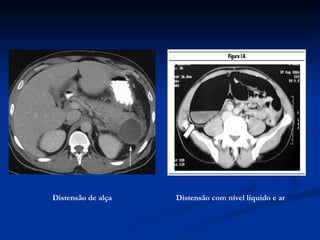

Distensão de alça   Distensão com nível líquido e ar